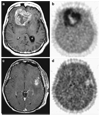

The success of cancer therapy can be difficult to predict, as its efficacy is often predicated upon characteristics of the cancer, treatment, and individual that are not fully understood or are difficult to ascertain. Monitoring the response of disease to treatment is therefore essential and has traditionally been characterized by changes in tumor volume. However, in many instances, this singular measure is insufficient for predicting treatment effects on patient survival. Molecular imaging allows repeated in vivo measurement of many critical molecular features of neoplasm, such as metabolism, proliferation, angiogenesis, hypoxia, and apoptosis, which can be employed for monitoring therapeutic response. In this review, we examine the current methods for evaluating response to treatment and provide an overview of emerging PET molecular imaging methods that will help guide future cancer therapies.